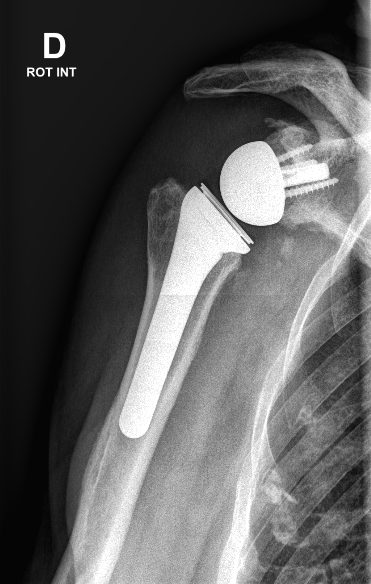

Description

La prothèse d’épaule est une opération visant à remplacer l’articulation de l’épaule (articulation entre l’humérus et l’omoplate) par un implant artificiel, lorsque celle-ci est gravement endommagée. Elle est indiquée principalement en cas d’arthrose de l’épaule très avancée provoquant des douleurs et une perte de mobilité importantes, en échec de traitement médical. L’arthrose de l’épaule correspond à l’usure du cartilage recouvrant la tête de l’humérus et la cavité de l’omoplate (glène). Quand ce cartilage est détruit, les os frottent l’un contre l’autre, entraînant des douleurs et une limitation des mouvements du bras. Parfois, la mise en place d’une prothèse d’épaule peut également être proposée après une fracture complexe de l’humérus (fracture du haut de l’os du bras) qui ne pourrait pas être reconstruite correctement autrement, ou en cas de rupture massive et irréparable des tendons de la coiffe des rotateurs associée à une arthropathie (arthrose par insuffisance des tendons). Il existe deux grands types de prothèses d’épaule : la prothèse anatomique (qui reproduit la forme naturelle, avec une tête humérale ronde articulée dans une cupule glénoïdienne creuse) et la prothèse inversée (qui inverse la disposition, avec une demi-sphère fixée sur l’omoplate et une cupule fixée sur l’humérus). Le choix dépend de l’état des tendons de l’épaule : la prothèse inversée est utilisée notamment lorsque les tendons de la coiffe sont détruits, car elle permet au muscle deltoïde de compenser l’absence de ces tendons. Dans tous les cas, l’objectif de la prothèse d’épaule est de soulager la douleur et d’améliorer la fonction du bras.

Technique chirurgicale

La mise en place d’une prothèse d’épaule s’effectue sous anesthésie générale le plus souvent (parfois complétée d’une anesthésie loco-régionale du bras pour le confort post-opératoire). L’intervention dure environ une heure et demie. Le chirurgien réalise une incision de quelques centimètres sur la face antérieure de l’épaule (vers le haut du bras). Il accède à l’articulation en écartant ou sectionnant partiellement certains muscles et tendons à proximité (notamment le muscle sous-scapulaire) de façon à découvrir la tête humérale et la glène. La tête de l’humérus abîmée est ensuite retirée chirurgicalement. La cavité glénoïde de l’omoplate est préparée (nettoyée et éventuellement agrandie) afin de recevoir un implant. Puis la prothèse est mise en place : la tige humérale munie d’une nouvelle tête ronde (ou d’une cupule, dans le cas d’une prothèse inversée) est implantée dans le canal médullaire de l’humérus, et la pièce glénoïdienne correspondante est fixée sur l’omoplate. Dans le cas d’une prothèse inversée, on aura fixé une demi-sphère métallique du côté de l’omoplate et une cupule au bout de la tige humérale, inversant ainsi l’articulation. Les composants sont généralement fixés à l’aide de ciment chirurgical ou par press-fit selon le modèle. Une fois la prothèse en place, le chirurgien vérifie la stabilité et le jeu de l’articulation, puis suture les muscles et referme la peau. Après l’opération, le bras est immobilisé dans une écharpe ou une attelle coude-au-corps pour protéger l’épaule nouvellement opérée.